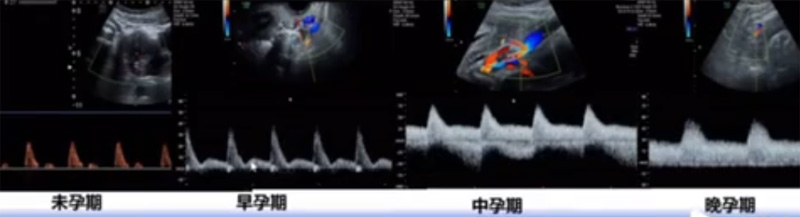

位于輸卵管的后下方,子宮兩側(cè)的后上方;借卵巢系膜與子宮闊韌帶后層相連。正常成人卵巢約4x3x2cm,跟睪丸的數(shù)值差不多,都是性器官,絕經(jīng)后卵巢萎縮變小、變硬。所以絕經(jīng)后婦女很難找到卵巢,主要功能:生殖和內(nèi)分泌功能分泌性激素。女性的第二性征。女性內(nèi)生殖器的血管分布,動(dòng)脈有子宮動(dòng)脈,卵巢動(dòng)脈,陰道動(dòng)脈,陰部?jī)?nèi)動(dòng)脈。靜脈它是與動(dòng)脈伴行。重要了解的是子宮動(dòng)脈,子宮動(dòng)脈是髂內(nèi)動(dòng)脈前干的重要分支,妊娠時(shí)候血流速度會(huì)增加的,為無(wú)創(chuàng)性檢查胎盤(pán)血管阻力的方法。未孕期頻譜為高阻力低舒張波形;正常妊娠時(shí)血流速度增加,血流阻力下降。